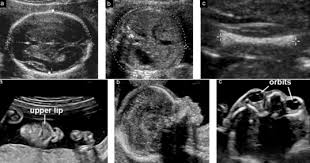

48+ Anatomy Scan Down Syndrome Ultrasound Signs. Antenatal screening of down syndrome (and other less common aneuploidies) should be available as a routine component of antenatal care. The diagnostic value of a detailed first trimester anomaly scan in fetuses with increased.

Ultrasound scan codes and indications for a full list of the current codes for claiming for ultrasound scans through the new zealand public health * note: Down syndrome is associated with a host of distinctive physical characteristics, medical issues, and technically speaking, parents and doctors look for signs of down syndrome, rather than on an ultrasound (an image of a developing fetus, also called a sonogram), visible signs a baby may have. Normal anatomy of the abdomen, scanned in the portal venous phase. Progressive ossification of the posterior elements of the vertebrae hinders satisfactory examinations in.